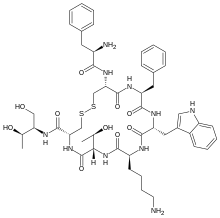

Others / unknown

- Adrenorphin

- Amidorphin

- Biphalin

- Casokefamide

- Casomorphins

- Cytochrophin-4

- DALDA (Tyr-D-Arg-Phe-Lys-NH2)

- Deltorphin I

- Deltorphin II

- Deprolorphin

- Dermorphin

- DPDPE

Structures

| Other or unknown opioid peptides | ||||

|---|---|---|---|---|

Adrenorphin Adrenorphin |

Amidorphin Amidorphin |

Casomorphin Casomorphin |

DALDA DALDA |

|

DPDPE DPDPE |

Endomorphin-1 Endomorphin-1 Endomorphin-2 Endomorphin-2 |

Gliadorphin Gliadorphin |

Morphiceptin Morphiceptin | |

Nociceptin Nociceptin |

Octreotide Octreotide |

Opiorphin Opiorphin |

Rubiscolin Rubiscolin |

TRIMU 5 TRIMU 5 |